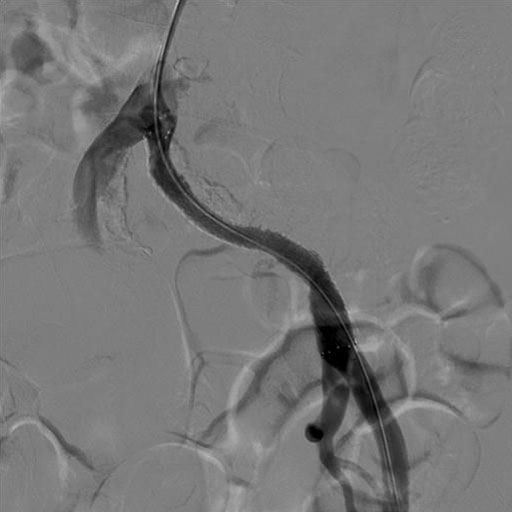

カテーテル治療(EVT)

直径2mmの管(カテーテル)を足の血管の中に挿入し、治療を行います。局所麻酔で1時間程度の治療時間です。血管の細くなった部分を、最適な治療方法(バルーン治療、ステント治療)で広げ、血流を改善させます。

治療前(左総腸骨動脈の閉塞)

治療後